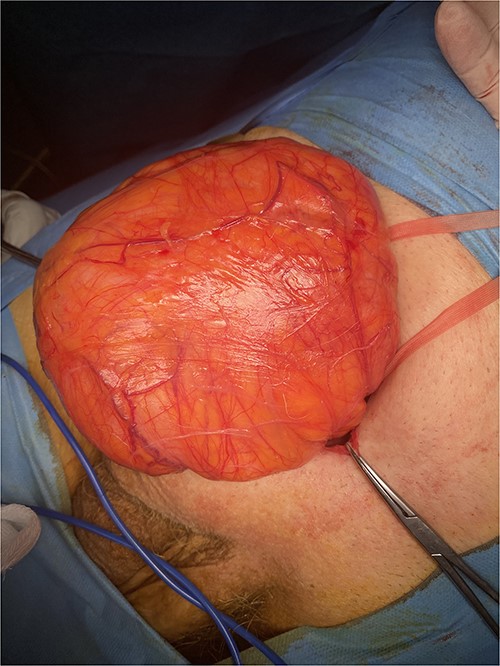

Following multidisciplinary consultation, a stent placement was considered too dangerous for ureteral injury because of acute angulation. Therefore, a primary repair of the inguinal hernia was decided. Because of the patient’s comorbidities, an open approach was favored. Intraoperative dissection revealed an indirect hernia with protrusion of a peritoneal sac containing small bowel loops and large amount of retroperitoneal fat (Fig. 2). The hernia sac containing the bowel loops and ureter was reduced without opening the sac to avoid iatrogenic injury of the ureter. The hernia was repaired with mesh placement according to the Lichtenstein technique (Fig. 3). The postoperative course was uneventful, with resolution of fever and gradual decrease of inflammatory markers. The patient was discharged safely on the fourth postoperative day, with complete resolution of hydronephrosis and normal renal function. Within a 6-month follow-up, no other complication was reported.

Intraoperative image showing the large hernia containing a large amount of retroperitoneal fat.